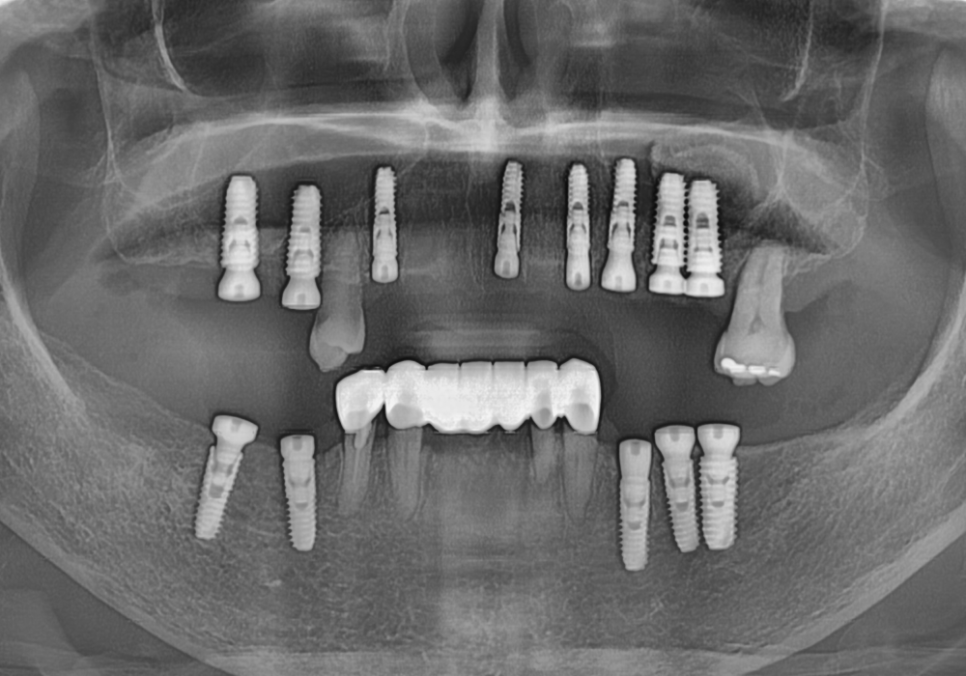

파노라마와 CT를 통해 살펴보니

뿌리 끝에 염증이 가득 잡혀 있었죠.

231211

230817(전) 240403 (후)

다행히 뼈이식 부위도 잘 자리를 잡았고

임플란트도 아주 튼튼하게 고정된 것을 확인 후

보철을 올려드렸습니다.